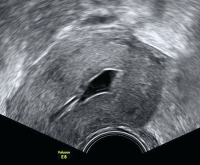

Ultraschall-Serometra

Abbildung 2: Serometra unter IVF-Stimulation: Nach Fehldosierung bildete sich eine Ansammlung eher echodenser Flüssigkeit im Cavum uteri, sodass der Zyklus abgebrochen werden musste.